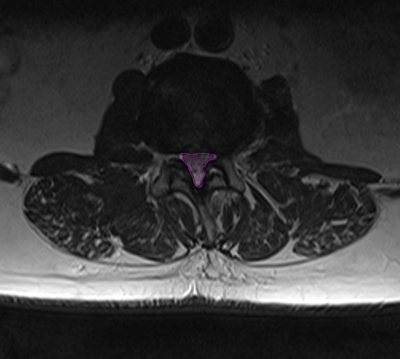

Φυσιολογικός ευρύς σπονδυλικός σωλήνας αριστερά (πράσινο) με άφθονο χώρο γύρω από τα νεύρα (βέλος). Στενός σπονδυλικός σωλήνας δεξιά με συμπίεση των νεύρων.